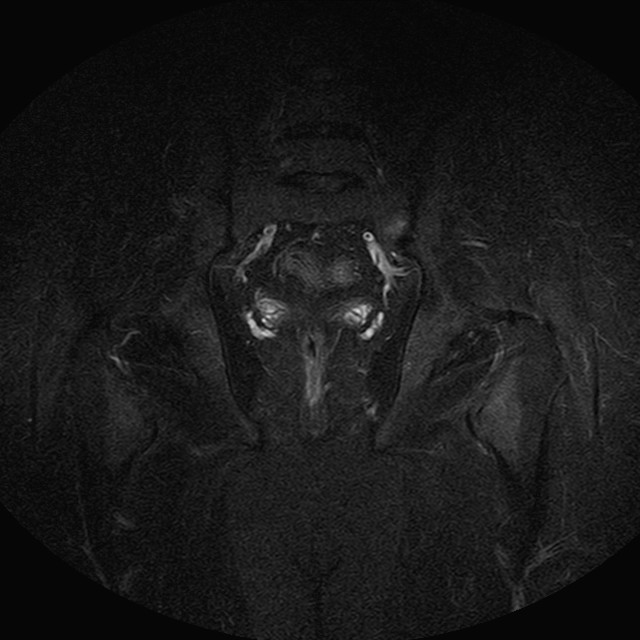

Esami: RMN BACINO

eSTIR

Evidenti e simmetriche alterazioni osteofitosiche in regione coxo femorale con riduzione delle rime articolari. Degenerazione completa del cercine glenoideo. Non attuali segni di versamento articolare. Non segni di edema osseo che escludono attuale algodistrofia od osteonecrosi. Lieve e simmetrica riduzione del trofismo della muscolatura glutea.